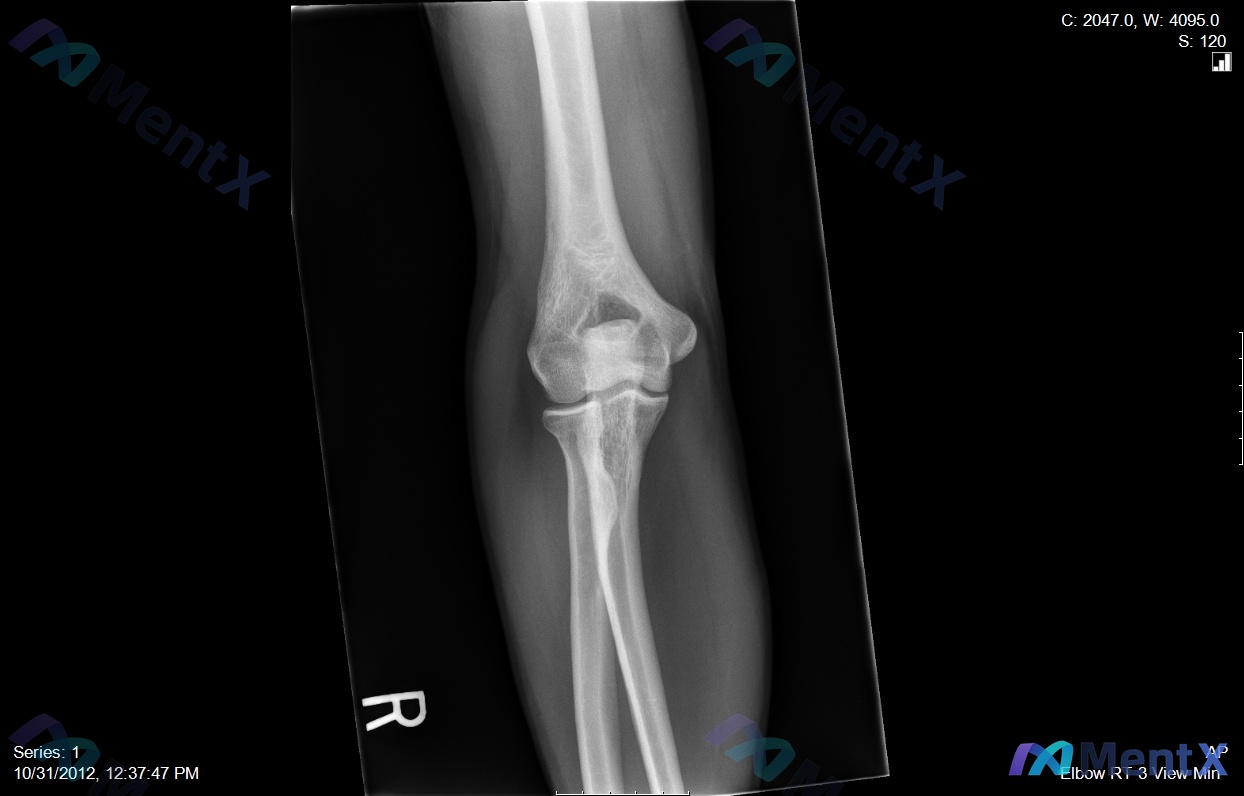

整理了一个挺有警示意义的病例,核心是「别被带偏,抓死核心体征」—— --- 病例基本情况 - 患者:35岁男性木匠 - 主诉:右肘前窝疼痛,用螺丝刀时明显加重 - 病程:6个月+,规范保守治疗(休息、抗炎、理疗)无效 关键体格检查 这个是破局核心: ✅ 钩试验(针对桡神经浅支卡压)正常 ❌ 但抗旋后...